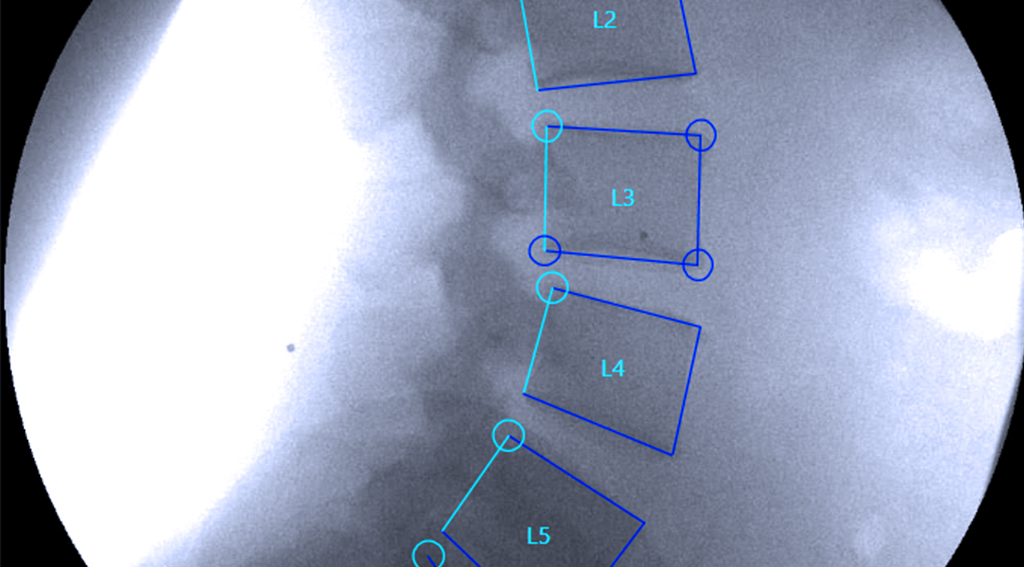

Vertebral Motion Analysis, or VMA®, is an FDA-cleared motion-based spine diagnostic that shows how the spine behaves in real time. Instead of taking still pictures like standard X-rays or MRIs, VMA captures continuous imaging as the patient gently bends forward, backward, and side to side.

Using a surgical-grade C-arm and proprietary software, VMA measures the movement of each vertebra with sub-millimeter accuracy. This reveals spinal ligament injuries and mechanical instability that are invisible on imaging at rest.

A surgical C-arm takes continuous images at eight frames per second throughout the bending cycle.

Specialized software tracks and measures:

- Vertebral translation (sliding)

- Angular rotation

- Excessive motion patterns

- Segmental instability

- Motion asymmetry

- Abnormal load distribution

- Measurements are accurate within 0.5–0.7 mm, far beyond the sensitivity of standard imaging.